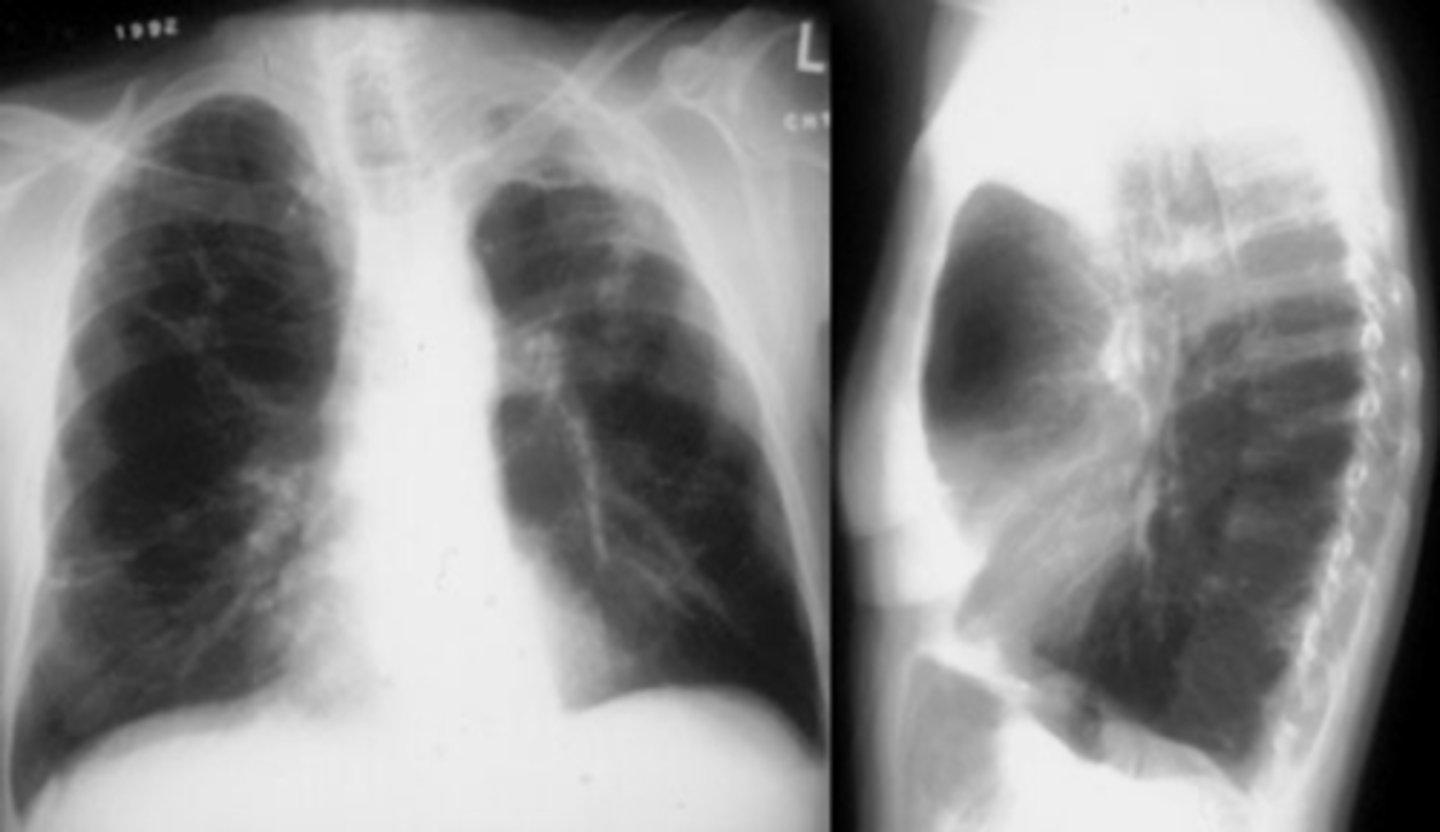

COPD/Emphysema

knowt flashcard image